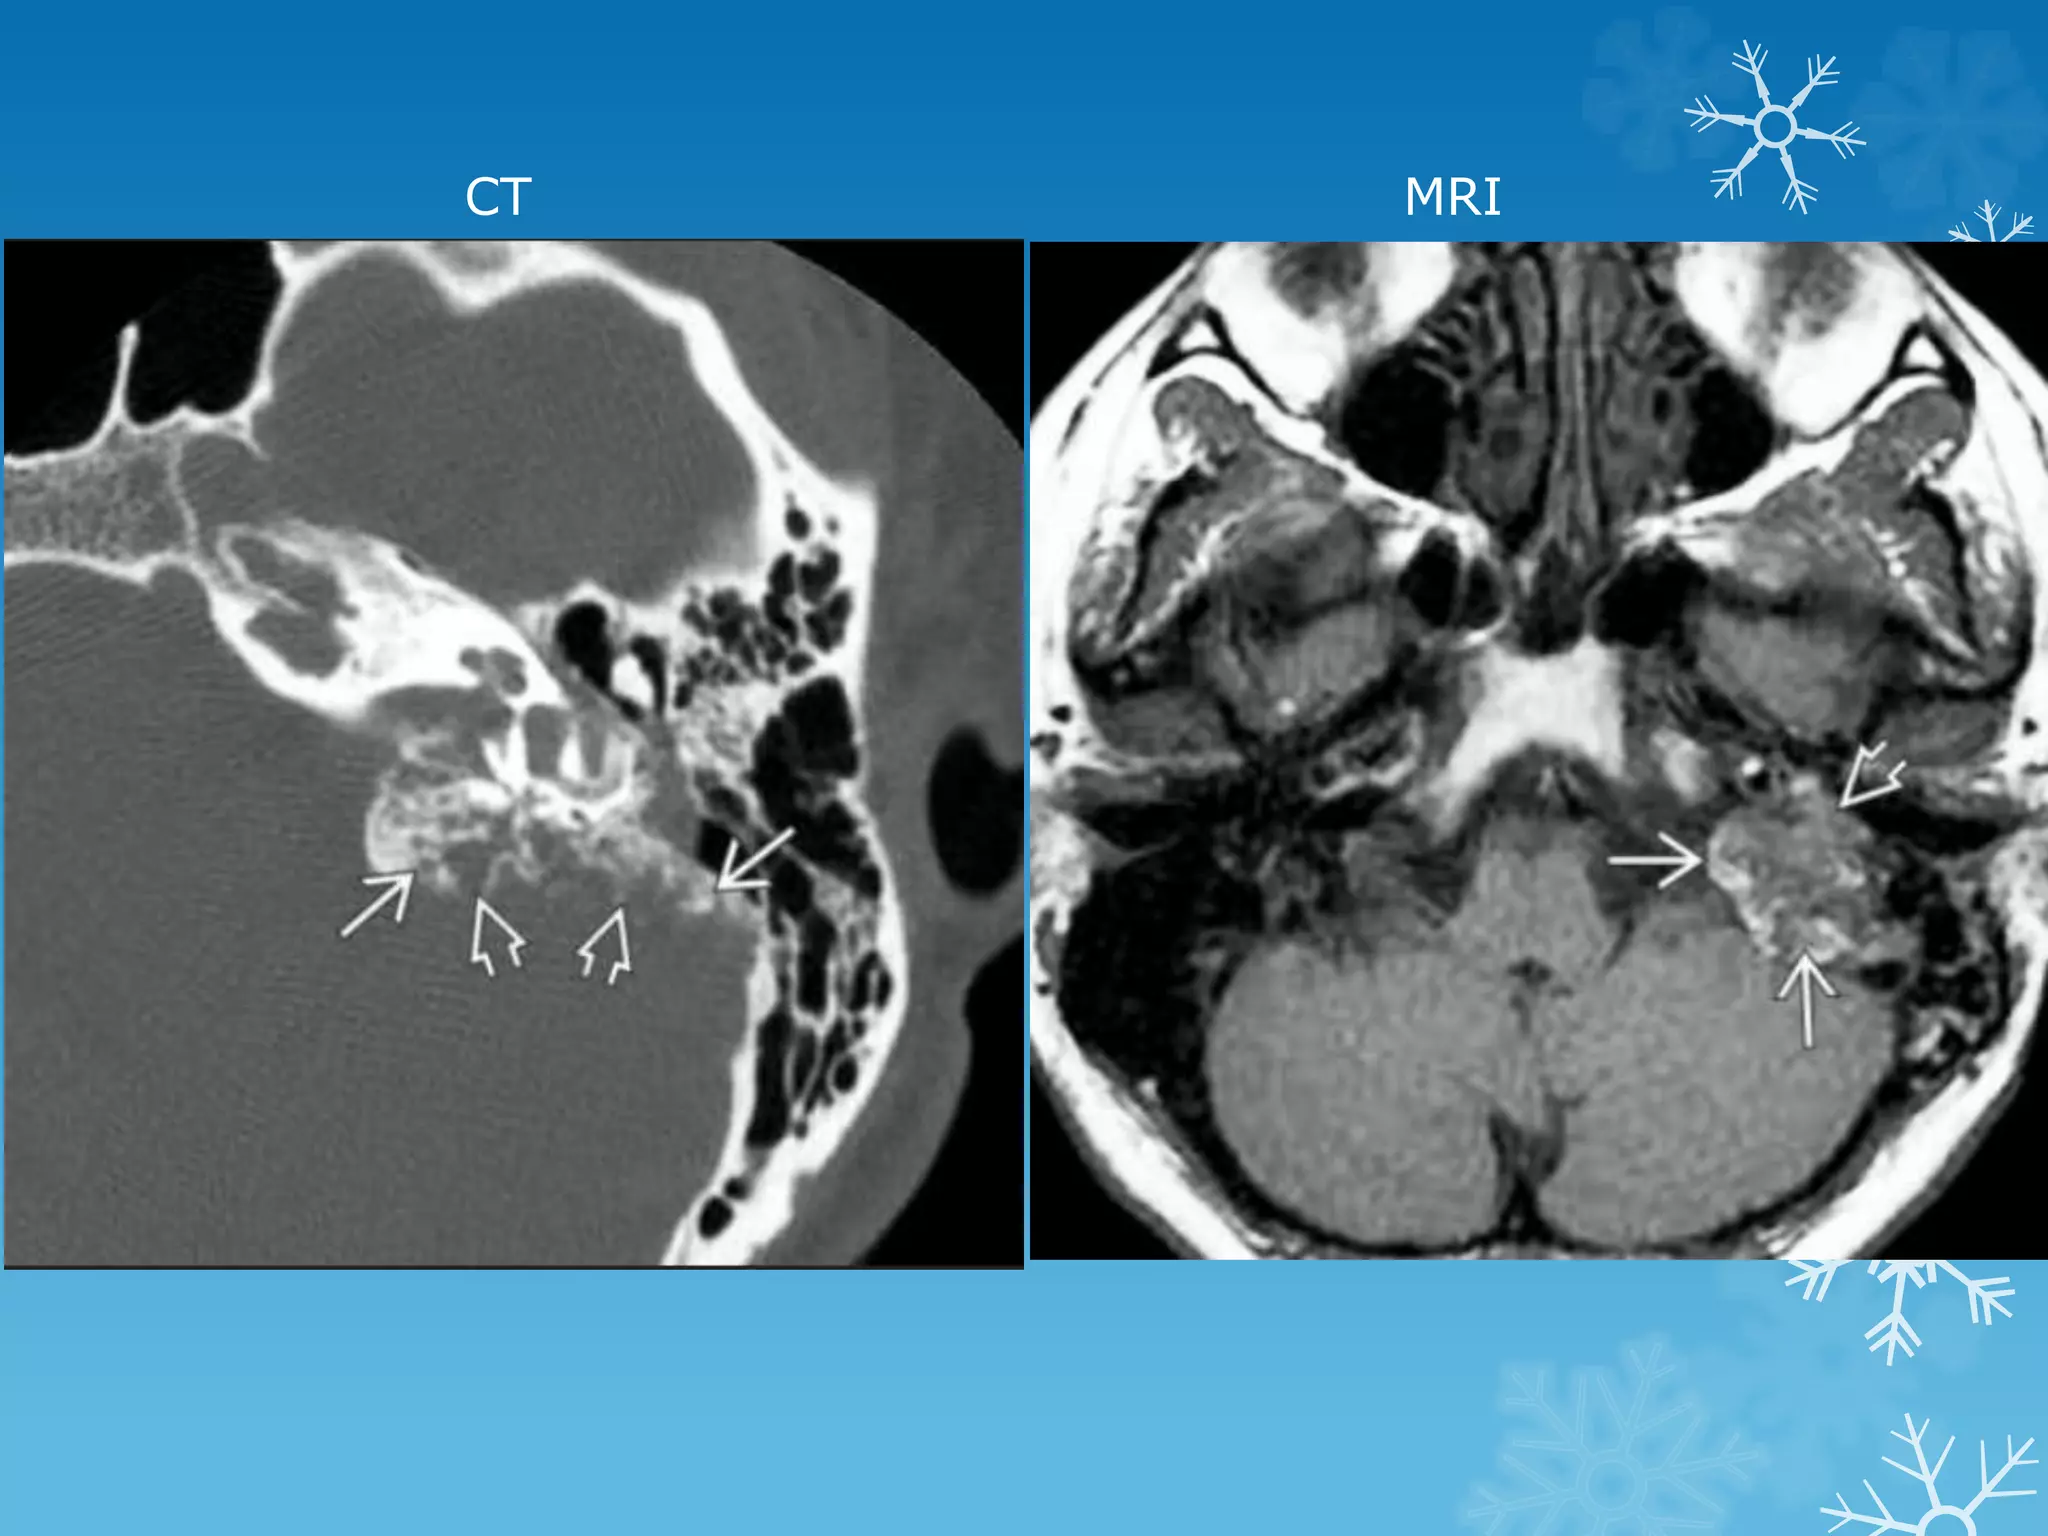

CT MRI

Endolymphatic sac tumors (ELSTs)

seven-year-old male patient with pulsatile tinnitus

Aberrant internal carotid artery

Some authors suggest that the reason could be the absence of the

hypotympanic bony plate because of a congenital failure of ossification.

With age, as the artery elongates and becomes tortuous, it protrudes

through the defect into the tympanic cavity.

Others suggest that the cervical ICA never develops and an aberrant carotid

artery forms when the inferior tympanic artery (a branch of the ascending

pharyngeal artery) enlarges to supply the territory of a cervical carotid

artery. The inferior tympanic artery runs through the middle ear and then

joins the horizontal petrous carotid artery. The so-called aberrant carotid

artery is, in fact, the markedly hypertrophied inferior tympanic artery.